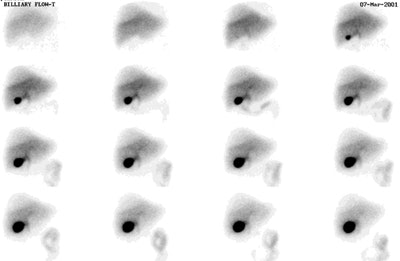

On the normal scan by about 5 minutes the liver activity should exceed cardiac blood pool, and by 10 minutes the cardiac blood pool activity should be gone. Persistent blood pool activity indicates hepatocellular dysfunction. Biliary activity is typically seen by 15 minutes and over 90% of normal studies demonstrate the gallbladder within 30 minutes. About 80% of normal subjects show small bowel activity within 60 minutes,and all show it within 90 minutes. If activity is seen within the gallbladder, but not in the small bowel by 90 minutes of the study, Sincalide may be used to expedite small bowel visualization and measure gallbladder ejection fraction. In patients with significant jaundice, do not confuse renal excretion for GB activity- always check lateral view as the GB will be anterior and renal activity posterior.

Normal Hepatobiliary Exam: A normal hepatobiliary exam demonstrating prompt hepatic tracer uptake and normal excretion into the gallballder and small bowel. There is breast attenuation over the upper portion of the right lobe of the liver. Click the image to view the cine exam (100KB). Case courtsey of Dr. Jamie Montilla, MD |